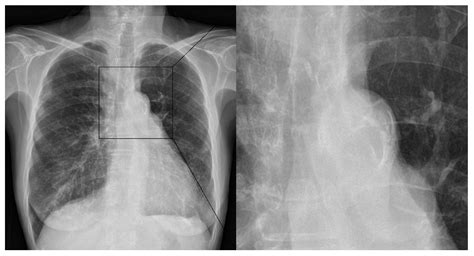

So, how do doctors figure out if you have aortic elongation with calcification ? The good news is that there are several ways to detect these changes, and often they are found incidentally during imaging tests done for other reasons. X-rays can sometimes show calcification in the aorta, especially in the chest or abdominal regions, appearing as white lines. However, X-rays aren’t always detailed enough to assess elongation or the extent of calcification accurately. A more common and informative tool is an ultrasound . Abdominal ultrasounds are frequently used to screen for aortic aneurysms, and during this scan, the radiologist can also assess the aorta’s length and look for calcification. Chest ultrasounds can also provide some information about the thoracic aorta. Computed Tomography (CT) scans are excellent for visualizing the aorta. A CT scan provides detailed cross-sectional images of the body, allowing doctors to precisely measure the aorta’s length, assess its curvature, and clearly see the pattern and extent of calcification. Contrast dye is often used to make the blood vessels stand out even more. Magnetic Resonance Imaging (MRI) is another powerful imaging technique that can provide detailed images of the aorta without using radiation. It’s particularly good at showing the structure of the aorta and can also detect calcification and elongation. Sometimes, doctors might use echocardiography (an ultrasound of the heart) to visualize the aortic root and the ascending aorta, especially if they suspect issues related to the valves or the proximal part of the aorta. If you have risk factors for cardiovascular disease, like hypertension, high cholesterol, or diabetes, your doctor might order these imaging tests as part of a regular health assessment or if you’re experiencing certain symptoms. Often, calcification is noted as an incidental finding on scans performed for other medical conditions. The key is that a healthcare professional reviews these images and interprets them in the context of your overall health. They’ll look for specific signs like increased tortuosity, loss of the normal aortic contour, and visible calcium deposits along the vessel walls. Early detection is key, as it allows for timely intervention and management of the associated risks.